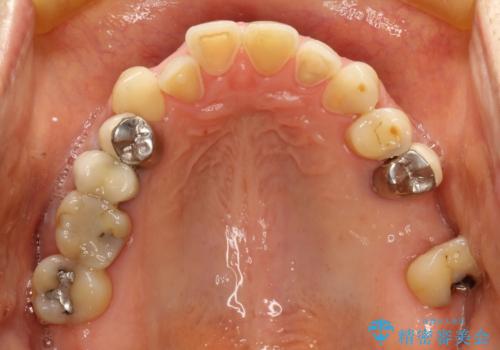

反対咬合や欠損を治療したい インビザライン矯正とオールセラミックブリッジ

- 虫歯治療がうまく進まないとのことで来院された患者様です。

虫歯治療や欠損補綴治療も必要でしたが、前歯が反対咬合であったので、セラミッククラウンやブリッジによる治療と並行して矯正治療を提案しました。

仕事柄海外出張が多いとのことで、虫歯治療後にインビザラインにて矯正治療を行うこととしました。

海外出張にとどまらず海外赴任もあり、途中2度の妊娠もあったため、治療には非常に長い期間を要することとなりました。